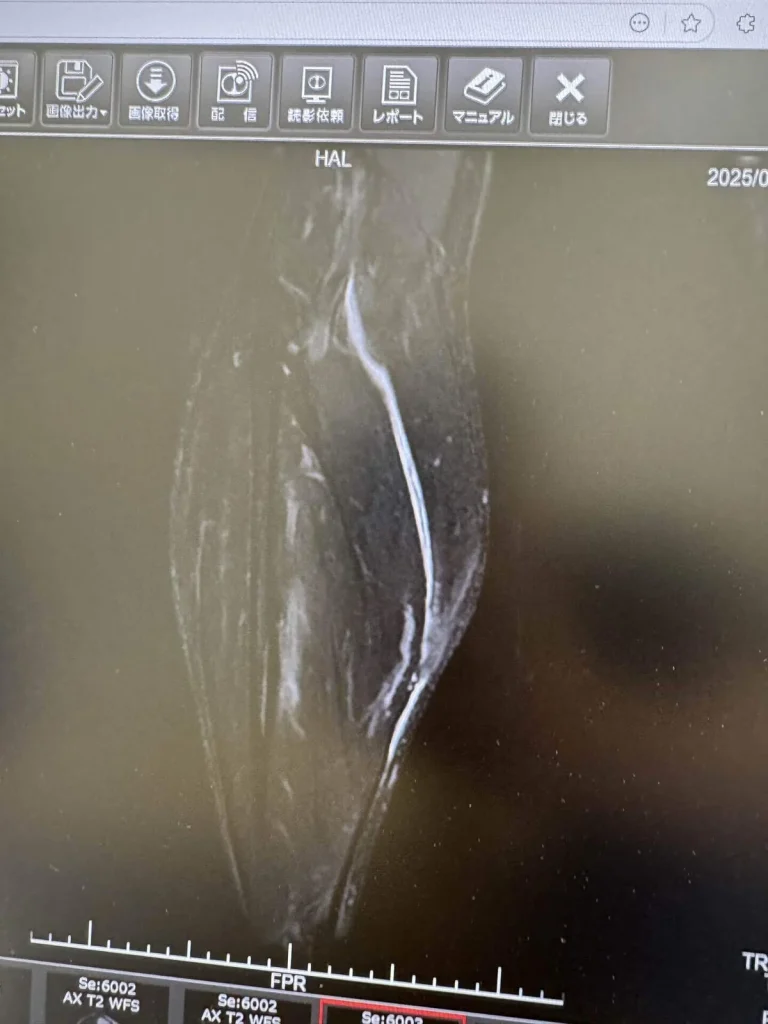

M R Iも撮って、診断結果は全治1ヶ月。

後日、検査してみると骨挫傷という骨折の一歩手前の状態でした。